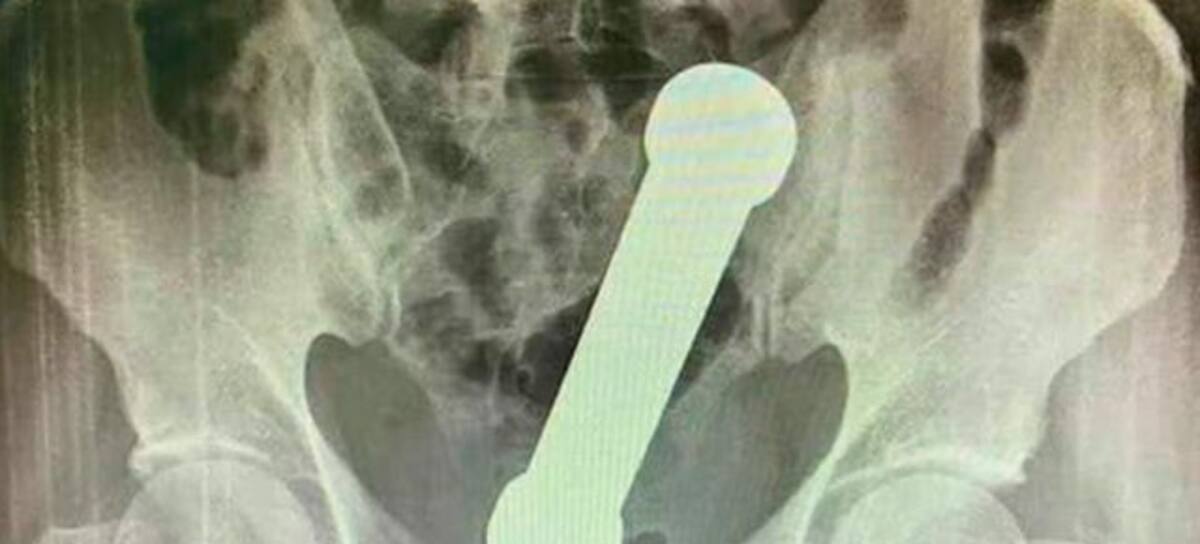

(Foto:International Journal of Surgery Case Reports)

Los médicos hicieron un examen manual y se dieron cuenta de que algo extraño estaba invadiendo el cuerpo del hombre, así que decidieron realizar una ecografía abdominal, descubriendo que tenía una pesa de gimnasio dentro de su cuerpo.

La pesa tenía casi 8 pulgadas de largo (20 cm) y estaba alojada exactamente en la parte donde el colon se encuentra con el recto, según se evidenció en el exámen. Por lo que tuvieron que proceder y sedar al hombre para poder retirar el objeto, ya que no quería cooperar.

Fueron dos intentos los que tuvieron que realizar los especialistas, el primero fracasó ya que las pinzas quirúrgicas no lograban sacar la pesa. La segunda opción fue que un cirujano tuvo que introducir su antebrazo para agarrar la pesa de metal de 2 kilogramos y sacarla por el recto.